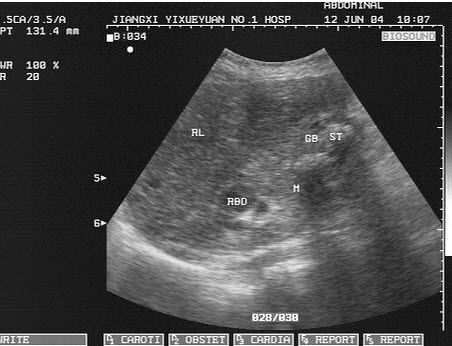

男,56岁,上腹经常疼痛不适多年。结合超声声像图,诊断为()

A.胆囊多发性胆固醇结晶

B.胆囊多发性息肉

C.胆囊多发性结石

D.胆囊癌

E.胆泥淤积